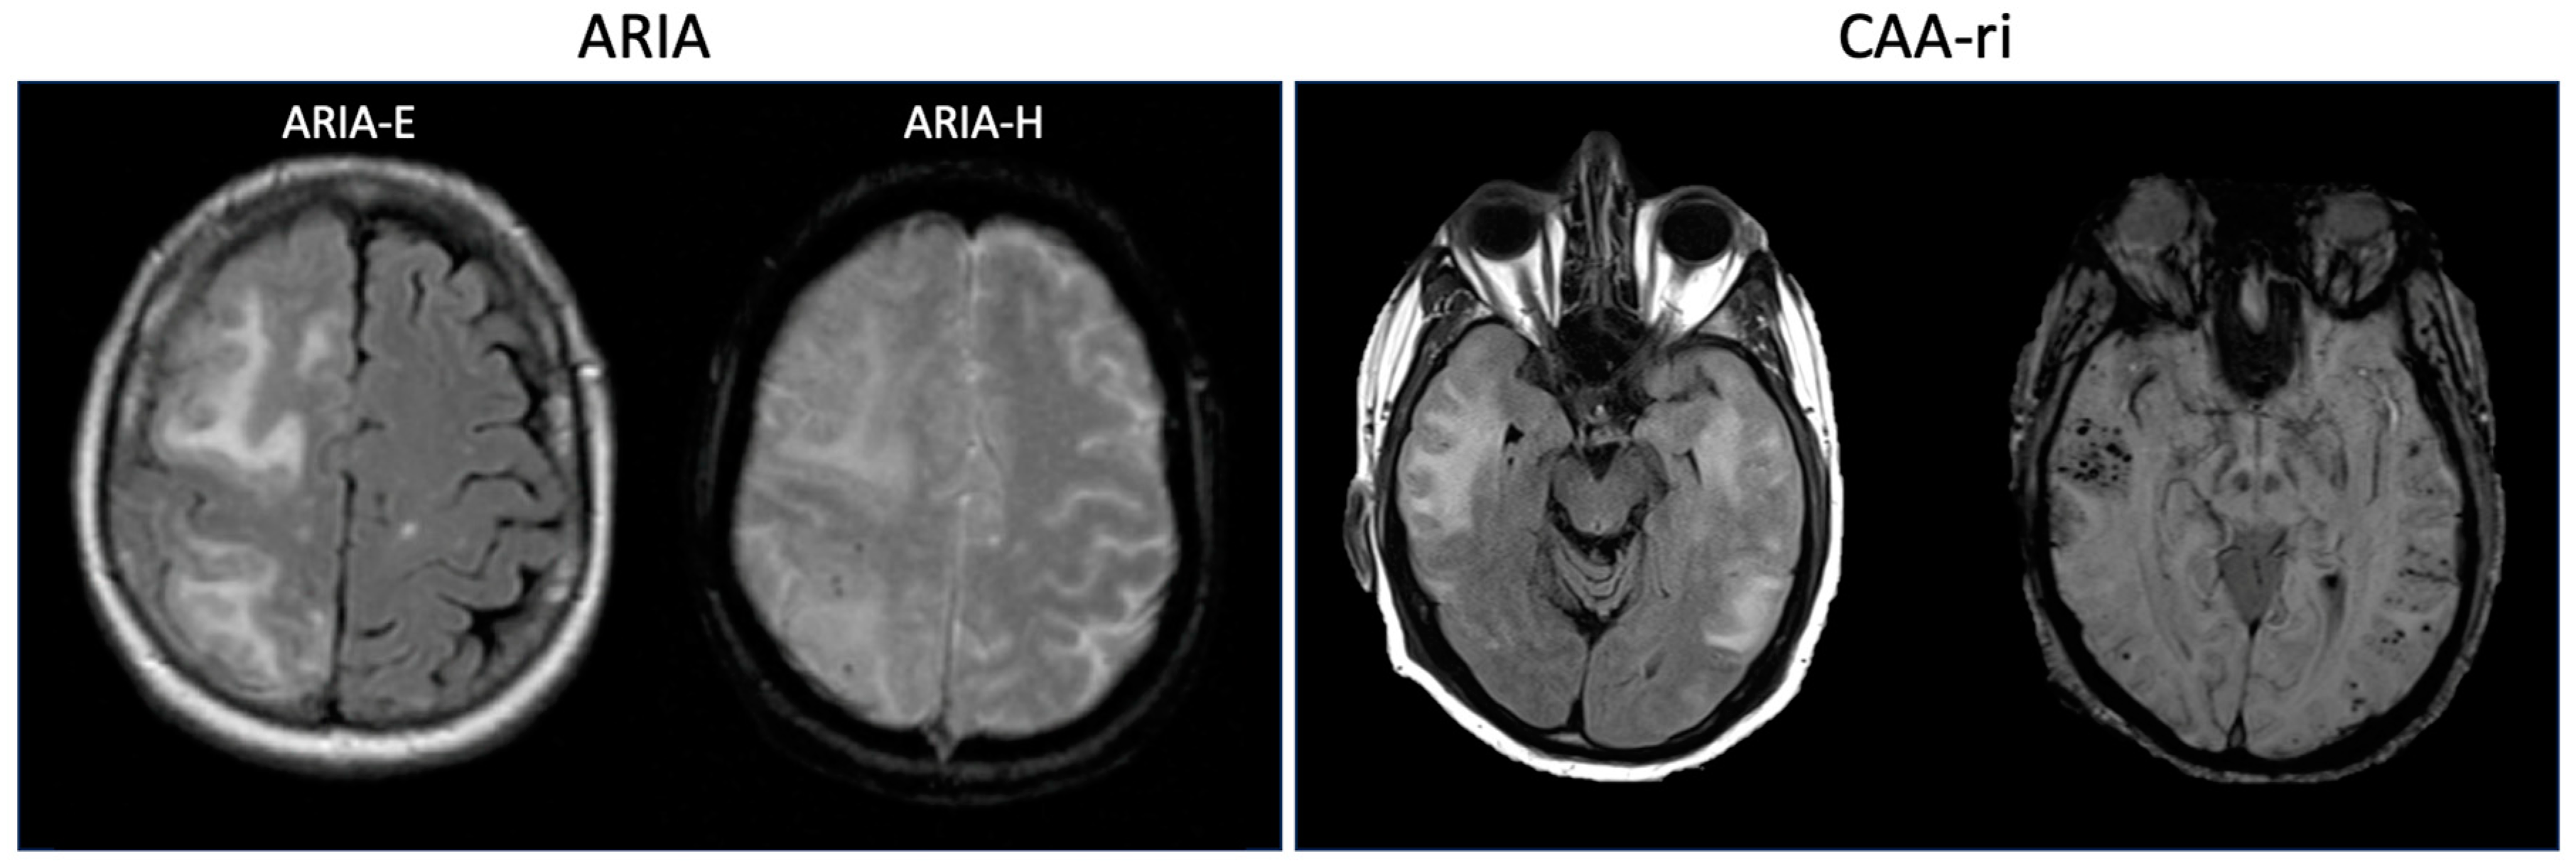

CAA-ri is a syndrome characterized clinically by acute or subacute encephalopathy, headaches, seizures and focal neurologic deficits and radiographically by evidence of asymmetric FLAIR hyperintensities and associated microhemorrhages on GRE or SWI sequences [48], similar in appearance to ARIA-E and ARIA-H, respectively (Figure 1). It was first described in 2004 by Eng and colleagues, who found that 7/42 patients with pathologically diagnosed CAA had evidence of perivascular inflammation [49]. These 7 patients all had encephalopathy and 71% had APOE ε4/ε4 alleles. Further studies have confirmed an association with the APOE ε4 allele [44]. Chung and colleagues proposed diagnostic criteria for CAA-ri [46] which were further refined by Auriel and colleagues [50]. Probable CAA-ri requires age ≥ 40 years old, presence of ≥1 of the following clinical features: headache, decrease in consciousness, behavioral change, or focal neurological signs and seizures, MRI with unifocal or multifocal WMH lesions (corticosubcortical or deep) that are asymmetric and extend to the immediately subcortical white matter and presence of ≥1 of the following corticosubcortical hemorrhagic lesions: cerebral microhemorrhage or cortical superficial siderosis. These updated criteria were found to have a sensitivity and specificity of 82% and 97%, respectively, when compared to pathologically confirmed CAA-ri [50]. Cerebrospinal fluid analysis in CAA-ri generally shows mild pleocytosis and elevated protein [51].

Figure 1.

(Left): Representative images from a patient with concomitant ARIA-E and ARIA-H (reproduced with permission from Sperling et al., 2011 [21]). The T2-FLAIR image on the left demonstrates regions of edema (ARIA-E) in the right frontal and parietal lobes, and the GRE image on the right demonstrates microhemorrhages (ARIA-H) in the right parietal lobe. (Right): Representative images from a patient with CAA-ri. The T2-FLAIR image on the left demonstrates edema in bilateral temporal lobes, and the SWI image on the right demonstrates multiple microhemorrhages within these regions.